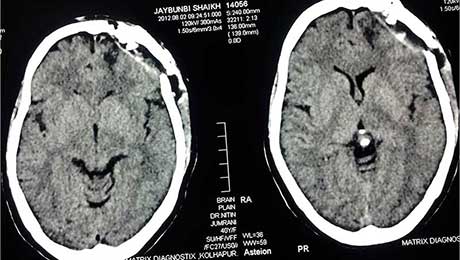

Post Op CT of Cavernoma